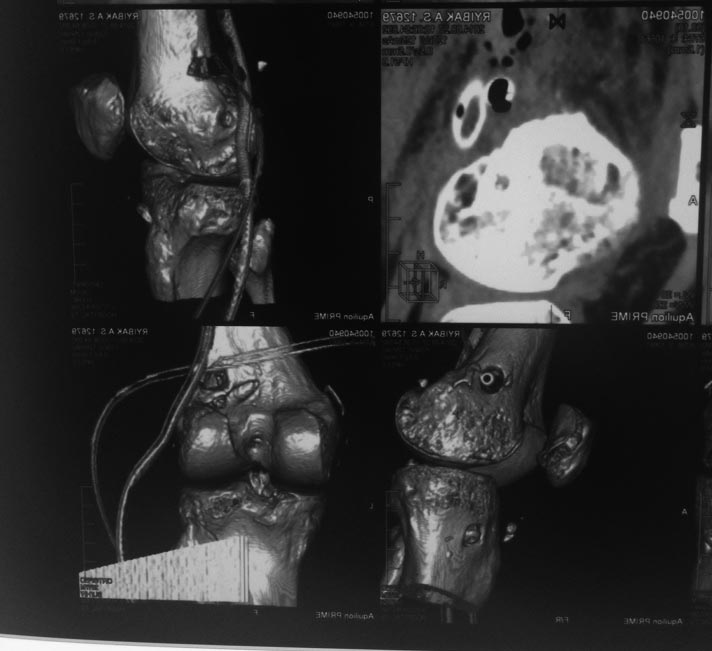

КТ после операции.

Есть остеопороз, но явного остеомиелита не наблюдается.